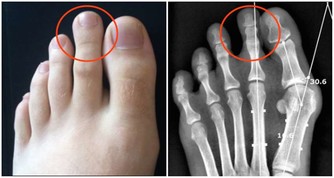

引起阻塞的原因乃是身體的毒素,亦即是有害人體的物質,如尿酸之類。

身體中的毒素,也可說是(污染物),多半是人體在吸收食品後,

進行新陳代謝中的產物,這就是『吃得多,病也多;吃得好,死得早』的道理,

它們往往停留在血管、肌肉、筋骨、關節以及臟腑的空隙中。